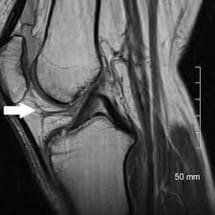

Le score de la douleur et le signal IRM d’IPFP (Infrapatellar Fat Pad) étaient réduits chez tous les sujets. En post-traitement à l’IRM pas de changement constant de lésions cartilagineuses, mais une position de la patella retrouvée significativement différente dans tous les plans : 1.7 mm plus haut (p=0.004), 1.2 mm plus médiale (patellar drift, p=0.0001) et 2° de plus vers le « varus » (patellar roll, p=0.001).

Une partie des douleurs retrouvées chez ces sujets pourrait s’expliquer de part la diminution de l’oedème du fat pad potentiellement lié à l’altération des structures adjacentes : inflammation de la synoviale, les lésions subchondrales, stress méniscal, etc.